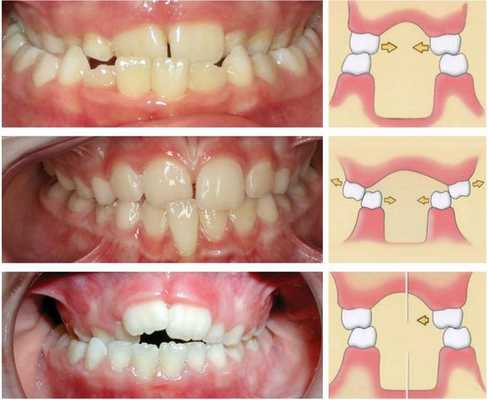

Пациентка Т. А., 16 лет. Диагноз: СЗЧЛА. Мезиальный правосторонний перекрестный буккальный прикус.

Учитывая хорошую форму зубных рядов, отсутствие выраженной скученности, торто-аномалий, лечение начато с установки дуги Cu-Ni-Ti (0,17x0,25). Уже через два месяца достигнута конгруэнтность зубных рядов, сопоставляющихся в конструктивном соотношении со множественными окклюзионными контактами.

В отличие от предыдущих случаев, у данной пациентки хирургический этап включал операцию только на нижней челюсти. В ходе операции мобилизованный срединный фрагмент перемещался кзади. При этом объем перемещения слева был вдвое больше, чем справа. По сравнению с вышеописанными случаями, у данной пациентки были самые неудачные условия и самый неблагоприятный, с точки зрения риска развития рецидива, прогноз. Проведение операции на нижней челюсти при мезиальном прикусе является самым спорным решением с позиций долговременной стабильности результата. Следуя такой логике, давление языка в условиях уменьшившегося объема полости рта должно привести к возникновению рецидива аномалии, особенно при «недостаточно надежной стабилизации» зубных рядов.

Тем не менее мы сочли возможным проведение операции при установленной в полости рта Cu-Ni-Ti-дуге. У этой пациентки прослежены наиболее отдаленные результаты из выборки пациентов, у которых применялся такой план лечения (3,5 года ретенции). А именно ненадежность достигнутого соотношения челюстей являлась одним из аргументов оппонентов данной методики.

Через 9 месяцев после операции удалены элементы ортодонтического аппарата. Установлены несъемные ретейнеры.

Пропорции лица были нормализованы. Прикус стабилен.